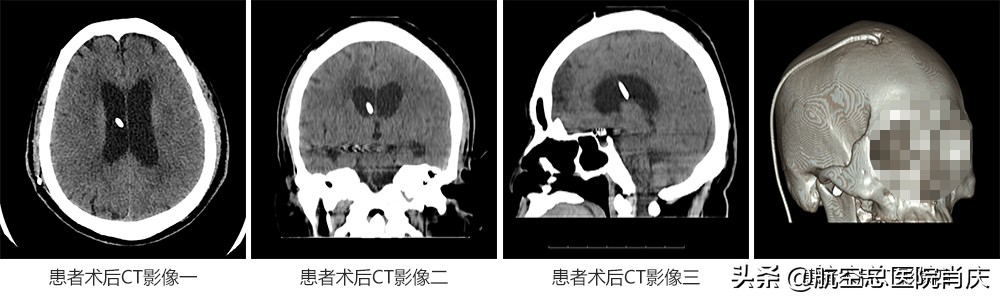

患者术后CT

患者术后第一天,情况良好,无明显头痛头晕,无恶心呕吐,无发热,进食水正常。术后第三天,四肢活动灵敏,沟通交流正常,建议多下地行走,观察病情变化。术后第六日,患者恢复良好,认知正常,自行行走,可准予出院。出院后动态观察患者症状,如有不适随诊,出院后一到三个月复查头颅CT明确。